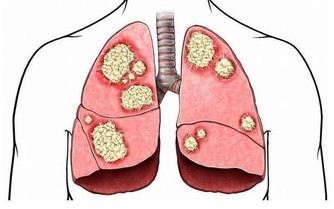

如此循環,血糖控制越來越差,飢餓感越來越重,終有一天會出現嚴重的並發症。

2.血糖控制不達標

低血糖:當機體血糖水平低時,產生飢餓感,刺激下丘腦攝食中樞,引起攝食中樞興奮,刺激人們進食提升血糖水平,滿足機體正常活動需求。

高血糖:血糖高時,胰島素相對不足,造成很少的葡萄糖帶給細胞維持正常功能代謝,另外血糖升高,血漿滲透壓升高,腎臟濾出葡萄糖會增多,而本來提供能量的糖被濾出去,身體缺乏能量造成飢餓感大增。